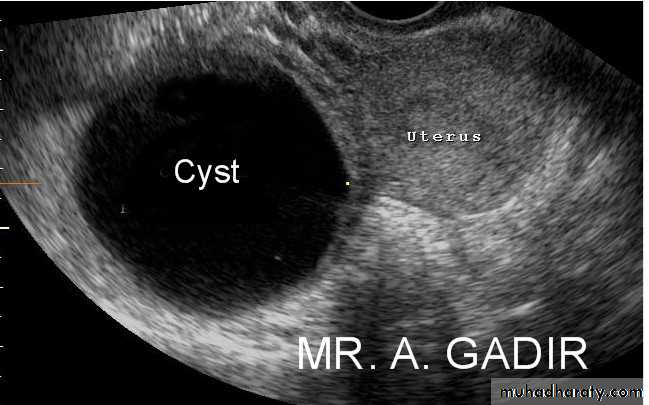

Lt. adnexal cystic mass- Luteal cyst(Lt. ovary):• Functional cysts of the ovary – Corpus Luteum cysts

Rt. ovarian simple cyst: